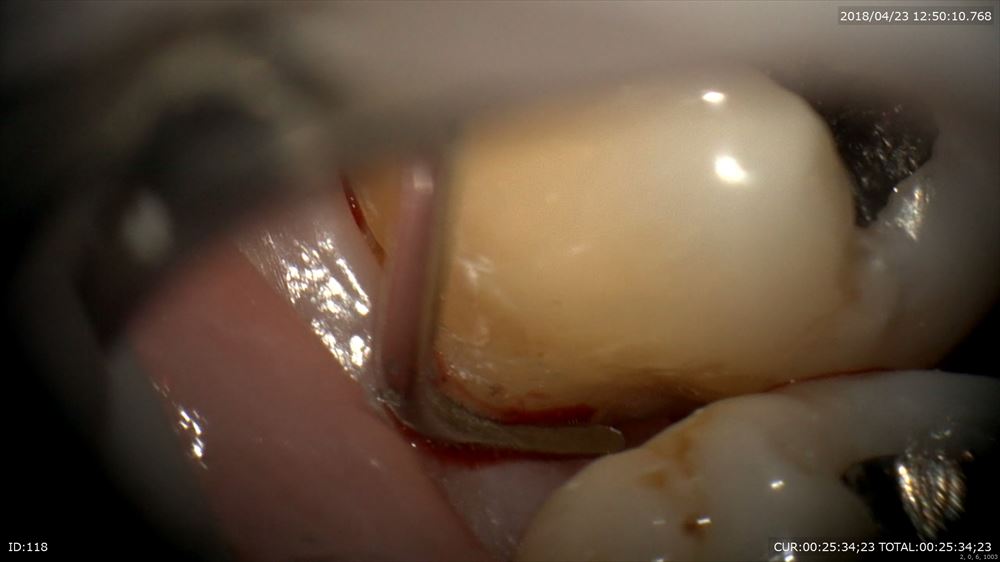

マイクロスコープでポケットの中の歯石(細菌)をみて

秋山勝彦先生ご発明の器具で剥離

この様に歯茎を切らずに歯肉溝からのアプローチ。この器具ミラーの役割もします。

歯根形態がこのように見えるからデブライドメントも、「なんとなく」ではなく歯根にきちっと合わせて行えます。